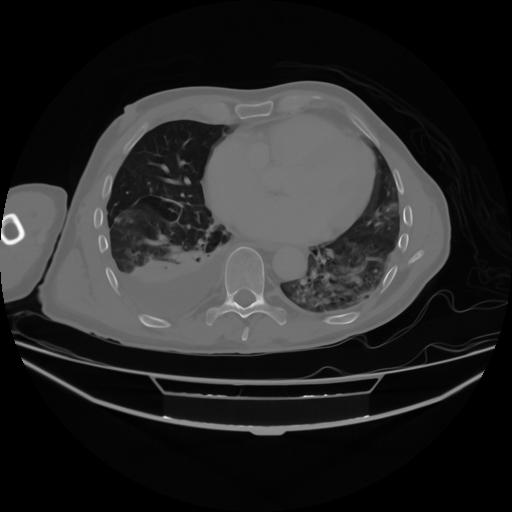

4 CUERPO,CE,Axial,3.0,CUERPO,,